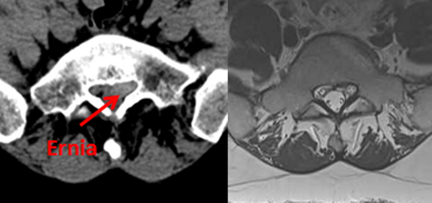

Ha effettuato una tac della colonna lombare con evidenza di voluminosa ernia discale L5-S1 sinistra con frammento migrato in basso.

A distanza di un anno eseguiva risonanza magnetica, con completa scomparsa del frammento erniario.

La regressione di un ernia discale può essere un fenomeno naturale e spontaneo. In questo caso non è scientificamente dimostrabile il rapporto con l’ozonoterapia sull’ottima evoluzione radiologica.